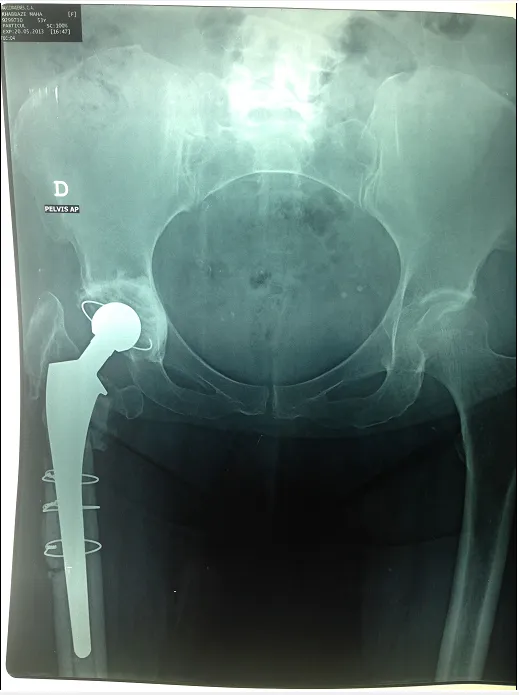

Dislocation of the hip prosthesis

We are talking about a dislocation of the hip prosthesis when the artificial femoral head comes out of the prosthetic acetabulum. Functional disability, pain and shortening of the lower limb are the main manifestations of dislocation of the prosthetic femoral head.

Radiological diagnosis is obvious most of the time and easy to detect.